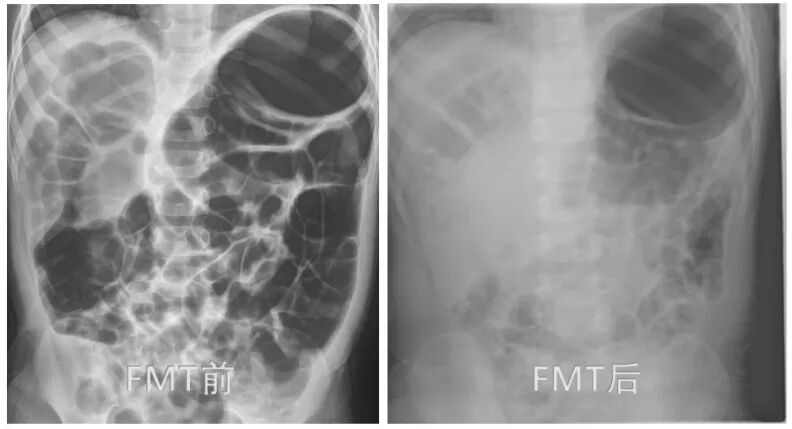

对于类似情况,在常规治疗不理想的情况下,可考虑进行肠道菌群移植术(FMT)。经过2个疗程的治疗,乐乐的腹胀症状明显好转,食欲逐渐恢复。术后6个月随访时,他的体重已追平同龄儿童水平,饮食恢复正常。从腹部平片可以清晰看出,乐乐接受肠道菌群移植术(FMT)治疗后,肠道充气显著好转,肠道功能得到明显改善。

图:患者接受肠道菌群移植术(FMT)治疗前后腹部平片对比